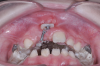

In reviewing this case more closely, the sequence usually starts with a space opening (Figure 12 through Figure 14). Palatal expansion is generally performed even without the presence of a posterior dental crossbite, as many patients with impacted maxillary central incisors are deficient in the development of the anterior portion of the maxilla.7,11 The use of sliding mechanics with open coils in conjunction with simple fixed systems is preferred to removable appliances since they deliver a light, continued force instead of an intermittent force.7 Interarch mechanics allow space to be gained for either the natural eruption or the surgical/orthodontic traction of the impacted maxillary central incisor.7 After palatal expansion, rigid structures, such as fixed transpalatal arches soldered to upper first molar bands, might first be used to anchor the active traction of the impacted tooth. Later, orthodontic fixed appliances reportedly have been used in the maxillary anterior to detail the position of the maxillary central incisor in the arch.11 Frequently, power arms are incorporated into palatal expanders.12 Fixed systems initially employ flexible nitinol wires and round stainless-steel wires. After initial leveling, rectangular stainless-steel wires have been used as part of several protocols to produce torque and place the roots of the resolved impacted central incisor in the proper position in its apical base.3,7,13 Orthodontic traction is conducted with different systems based on the preference of the clinician.3,7,10

Fig 12. After expansion of the maxillary arch, the modified palatal expander was used for traction of the impacted maxillary right central incisor. Fig 12: Palatal expansion to gain space in the premaxilla for the impacted maxillary right central incisor. Fig 13: Traction of the impacted maxillary right central incisor through a palatal orthodontic attachment and the use of a power arm incorporated in the expander. Fig 14: Detailing the position of the impacted maxillary right central incisor with orthodontic fixed appliances.

Figure 12

Fig 13. After expansion of the maxillary arch, the modified palatal expander was used for traction of the impacted maxillary right central incisor. Fig 12: Palatal expansion to gain space in the premaxilla for the impacted maxillary right central incisor. Fig 13: Traction of the impacted maxillary right central incisor through a palatal orthodontic attachment and the use of a power arm incorporated in the expander. Fig 14: Detailing the position of the impacted maxillary right central incisor with orthodontic fixed appliances.

Figure 13

Fig 14. After expansion of the maxillary arch, the modified palatal expander was used for traction of the impacted maxillary right central incisor. Fig 12: Palatal expansion to gain space in the premaxilla for the impacted maxillary right central incisor. Fig 13: Traction of the impacted maxillary right central incisor through a palatal orthodontic attachment and the use of a power arm incorporated in the expander. Fig 14: Detailing the position of the impacted maxillary right central incisor with orthodontic fixed appliances.

Figure 14